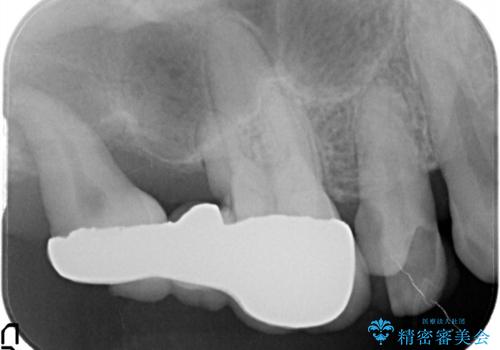

歯周病の進行した歯の抜歯。オールセラミッククラウン

最後方臼歯は根尖部まで歯周病が進行しており、抜歯を行なったのち、残存歯は歯周外科を行なったのちオールセラミッククラウンにて修復治療を行なっています。